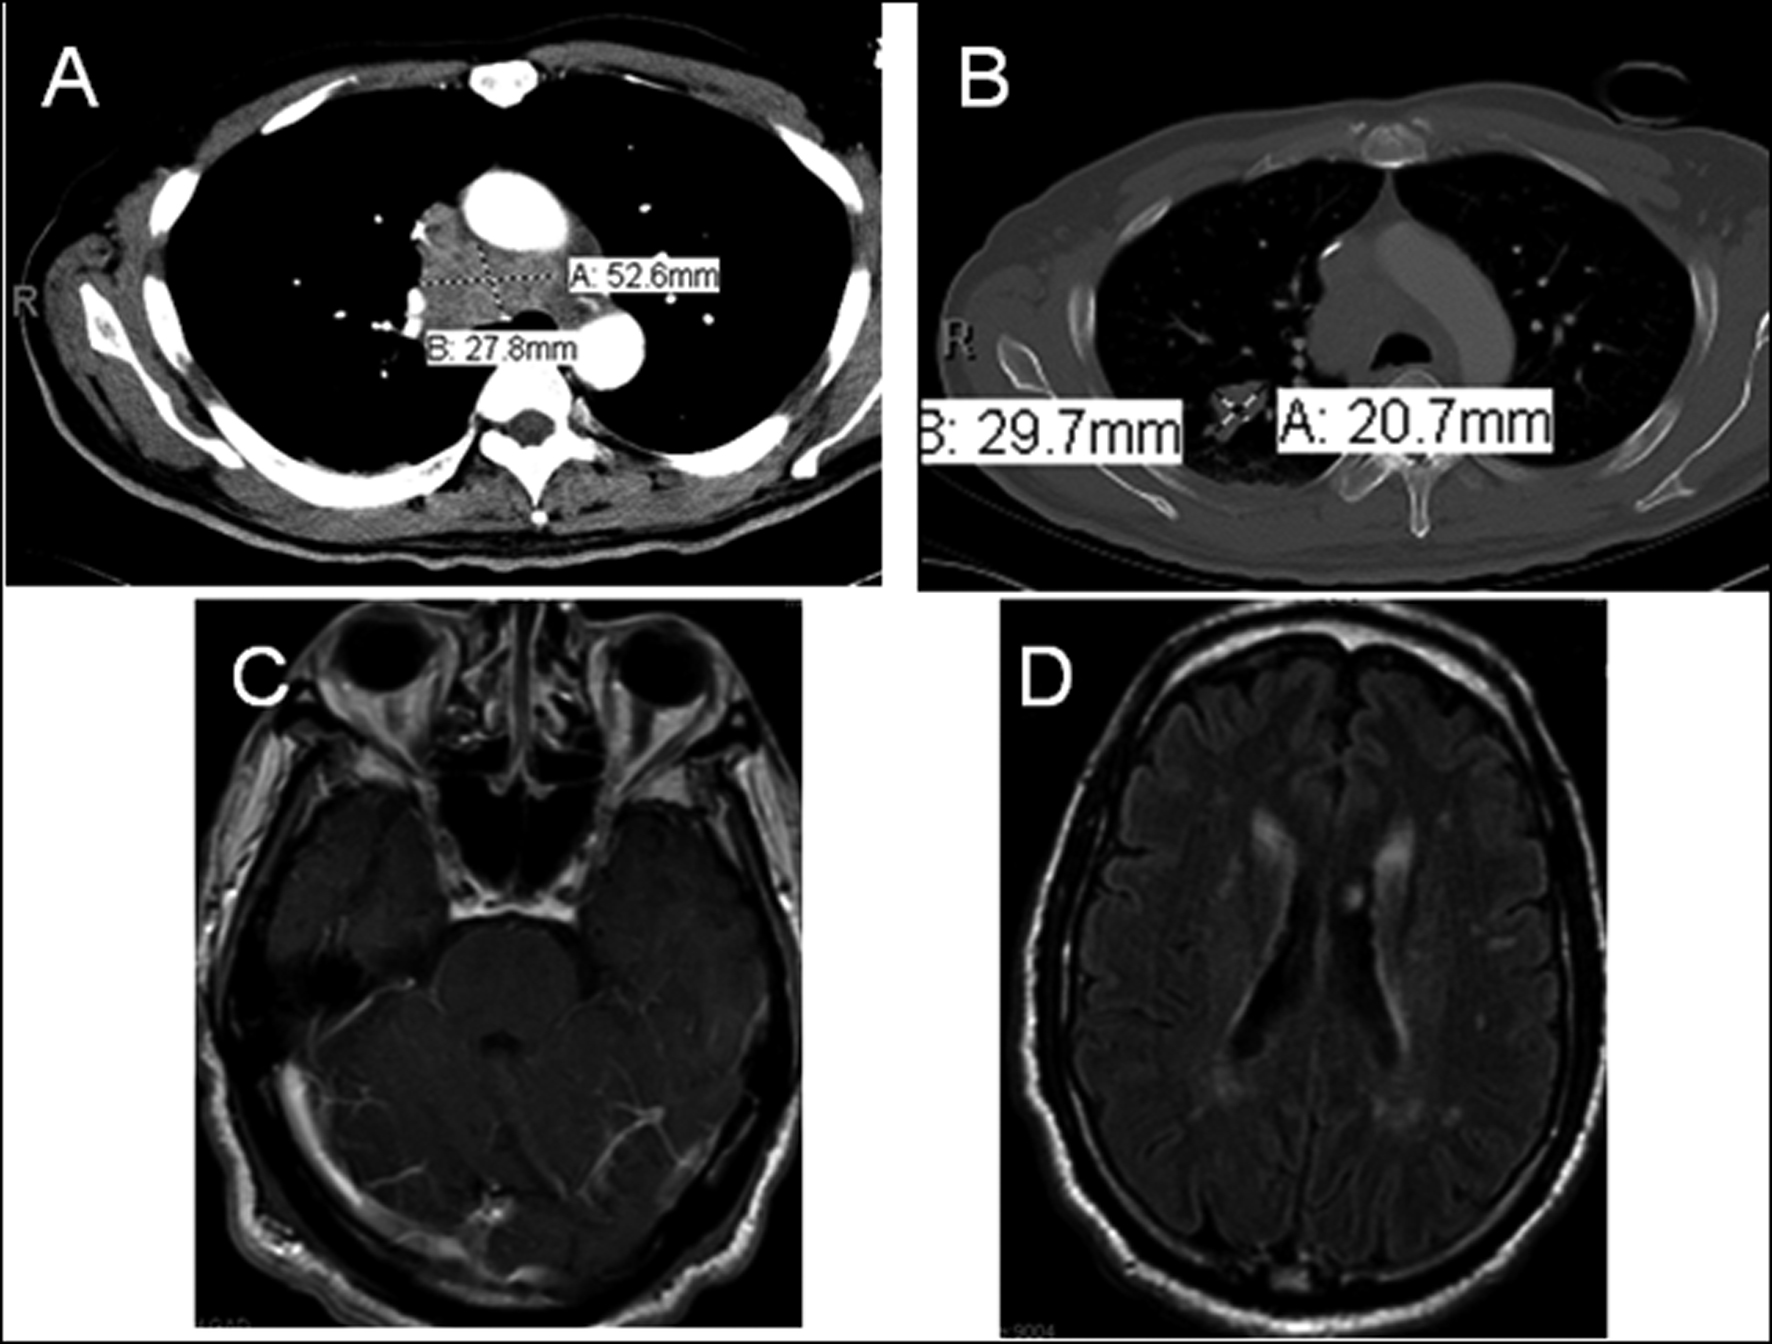

Diagnostic Approach to a Patient With Paraneoplastic Neurological Syndrome